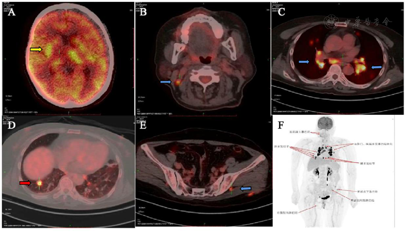

脑磁共振成像(MRI)显示双侧大脑半球、右丘脑、右颞下叶多发病变(图1A)。胸部CT图像显示纵隔和双肺门淋巴结肿大并伴有多个肺结节(图2A)。18f -氟脱氧葡萄糖(FDG)正电子发射断层扫描(PET/CT)显示右上颈部深淋巴结、门部、纵隔、多发肺结节、双侧髋关节肌间隙、左髋关节皮下软组织明显摄取FDG(图3)。超声(US)引导下左髋关节皮下软组织活检显示大量嗜酸性粒细胞及纤维血管增生,无法提供诊断线索。然后我们在局部麻醉下对纵膈淋巴结进行WANG™经支气管抽吸针。然而,标本中仅发现少量纤毛柱状上皮细胞,诊断仍不明确。最后在全身麻醉下行支气管超声引导下经支气管针抽吸(EBUS-TBNA)纵隔淋巴结,发现慢性肉芽肿性炎症,提示结节病诊断(图4)。

文献报道,约5%至26%的结节病患者会出现神经系统并发症,在尸检研究中,患病率高达27%[6],这种累及神经系统的结节病,被称为神经系统结节病(Neurosarcoidosis, NS)。临床上,神经系统结节病的诊断往往依靠结节病多系统改变伴随神经系统表现,但必须先排除特殊病原菌感染及恶性肿瘤。由于神经系统结节病的组织学证据不易获得,因而当临床上怀疑神经系统结节病时,应先寻找神经系统以外疾病受累的证据。本病例以神经系统症状嗜睡起病,发病期间存在不规则发热,头颅MRI表现为右侧额叶、两侧颞叶、桥脑右侧、双侧基底节及侧室旁异常信号影,右侧丘脑病变伴周围水肿,胸部CT纵隔窗表现为双肺门、对称性淋巴结肿大,纵隔淋巴结肿大,胸部CT肺窗示表现为双肺散在多发结节,超声内镜引导下的经支气管针吸淋巴结活检提示慢性肉芽肿性病变,排除特异性感染后考虑结节病。该患者糖皮质激素治疗后未再出现发热,嗜睡及认知功能均较前明显改善,复查胸部CT示双肺门、纵隔内多发肿大淋巴结及双肺结节均较前缩小,复查头颅MRI示丘脑病变较前明显好转。故本病诊断肺结节病、神经系统结节病明确[7]。